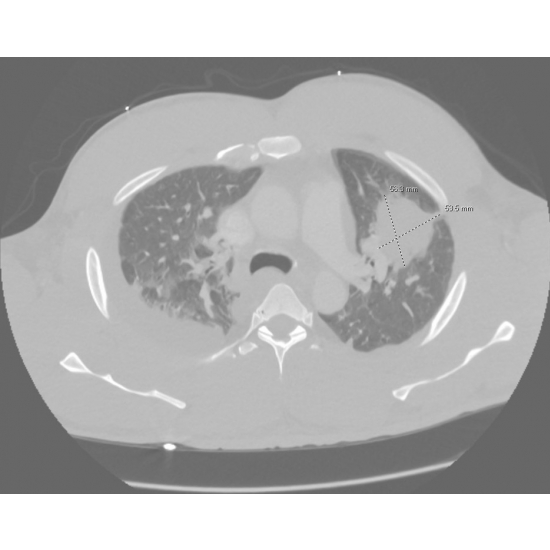

EKG demonstrated rightward axis and incomplete right bundle branch block. Echo found an EF of 60-65%, normal LV wall motion, moderate concentric LV hypertrophy, and mild to moderate dilation of the RV. Chest X-ray was notable for right pleural effusion, ill-defined airspace opacity in the left upper and mid lung zones, possibly an infectious/inflammatory process, cannot exclude neoplasm. Case Photo #1 CTA chest with contrast demonstrated 5.6cm x 5.4 mass causing severe narrowing of left upper lobe segmental pulmonary artery branches, as well as nodules. Case Photo #2 Thoracentesis was performed, and pleural fluid cultures were negative for growth, and cytology was negative for malignancy. Repeat CT chest with contrast done 11 days later showed a decrease in mass to 3.3 x 2.7 cm. Case Photo #3